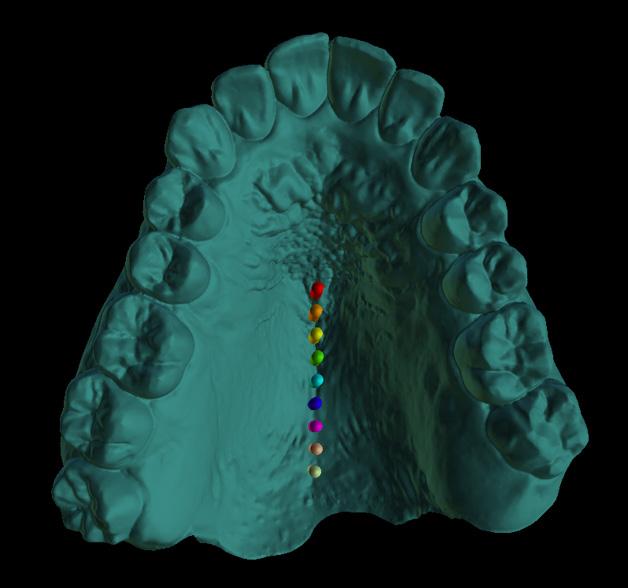

Standard orthodontic pretreatment records (T0) were obtained (Figure 1). The same operator obtained the lateral cephalogram and OPG using the same machine. The lateral cephalograms were traced manually with the standard technique by a single

investigator and a total of 06 skeletal, 11 dental, and 03 soft tissue parameters were measured. Selected patients were also subjected to Acoustic pharyngometry (AP) for a three-dimensional evaluation of the upper airway. Fixed orthodontic appliance (022” MBT PEA) was bonded on both maxillary and mandibular arch, with banding of first & second molars. A standard wire sequence was followed till the full slot engagement with SS wire (19 X 25”) was achieved. A complete set of records were made to register the beginning of the fixed functional phase (T1) (Figure 2). Forsus appliance (FFRD) was fitted for each patient, push rod hooked on the archwire between canine and 1st premolar in the maxillary arch and distal end of open coil spring connected with the ‘L’ pin to the 1st mandibular molar. Maxillary and mandibular components of the Forsus FRD were connected to provide a forward thrush to the maxilla and a backward thrust to the mandible during the closure of the mouth (Figure 3). The functional phase with Forsus FRD continued till the desired objectives were achieved i.e., achieving positive overjet as well as satisfactory improvement in soft tissue profile.

To enhance the skeletal effects of the Forsus appliance, the indirect anchorage was obtained using TADs (temporary anchorage devices), placed in the maxillary arch, distal to canine. Post-functional records were made after the removal of Forsus FRD (T2) (Figure 4). Fixed orthodontic therapy continued to settle the occlusion and patients were debonded (Figure 5).